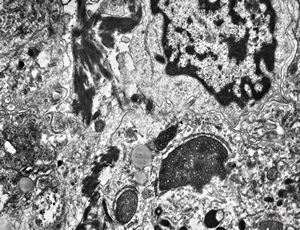

F,49y. | purulent meningitis- meningococcal v.s.